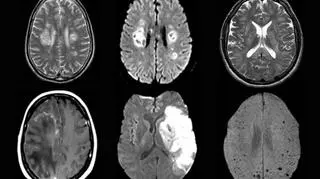

Skany mózgu opublikowane przez Kolegium Uniwersyteckie w Londynie (University College London)

Źródło: University College London

Od kwietnia do maja naukowcy zbadali 43 pacjentów leczonych w szpitalach Kolegium Uniwersyteckiego w Londynie, ich wiek wahał się od 16 do 85 lat. Wykazywali szereg objawów - od łagodnych po ciężkie. Wśród tych pacjentów naukowcy znaleźli 10 przypadków z "przejściową dysfunkcją mózgu" i majaczeniami, 12 przypadków z zapaleniem mózgu, osiem przypadków udarów i osiem przypadków uszkodzenia nerwów.

Ponadto u większości chorych, u których stwierdzono stan zapalny mózgu, rozpoznano chorobę ADEM (ostre rozsiane zapalenie mózgu i rdzenia). Przed pandemią zespół badawczy zdiagnozowałby w Londynie jednego pacjenta z tą chorobą na miesiąc. W okresie badań (kwiecień-maj) liczba ta wzrosła do co najmniej jednego przypadku w tygodniu.